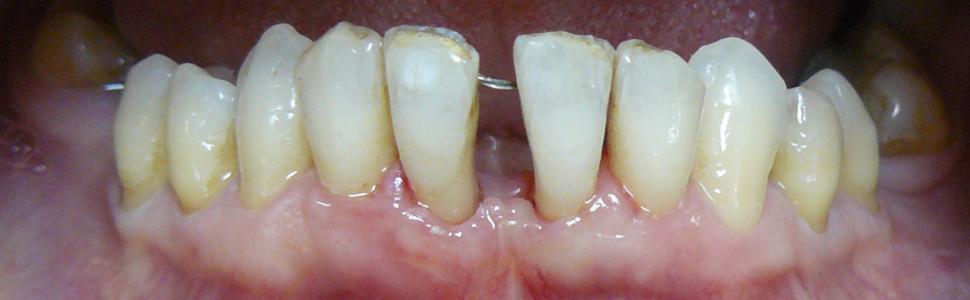

Z wywiadu ustalono, że pacjentka nieregularnie korzystała z opieki stomatologicznej, głównie było to leczenie próchnicy i profesjonalne oczyszczanie zębów. Jej stan zdrowia był ogólnie dobry, nie przyjmowała żadnych leków, a głównym problemem stała się zaburzona estetyka. W czasie badania klinicznego nie stwierdzono obecności stanu zapalnego, nie obserwowano krwawienia, głębokość kieszonek przyzębnych nie przekraczała 4 mm. Obserwowano niewielką ilość miękkich i twardych złogów nazębnych. Manifestacją zaawansowanej redukcji tkanek przyzębia były liczne recesje, ruchomość przyśrodkowych zębów siecznych górnych i dolnych na granicy I i II stopnia oraz migracja patologiczna skutkująca dysfunkcją żucia. Największe recesje obserwowano na powierzchni wargowej i mezjalnej przyśrodkowych zębów siecznych dolnych. W okolicy zęba 41 odpowiednio 3,5 i 6 mm, w okolicy zęba 31 odpowiednio 2 i 3,5 mm. Były to recesje typu 3 (RT3), dodatkowo występował deficyt dolnej brodawki centralnej typu 2 według Nordlanda i Tarnowa, ekstruzja zębów przednich z rotacją zęba 41 (ryc. 1) oraz diastema. Wykonane zdjęcie rentgenowskie ujawniło poziomą destrukcję części zębodołowej żuchwy w przestrzeni pomiędzy przyśrodkowymi zębami siecznymi dolnymi (ryc. 2). Pacjentka wymagała kompleksowej rehabilitacji, której głównym elementem było leczenie ortodontyczne i protetyczne. W pierwszej fazie zaplanowano jednak chirurgiczne pokrycie recesji, przygotowujące okolicę zębów siecznych dolnych do leczenia ortodontycznego. Celem była częściowa redukcja recesji dziąsłowych, poszerzenie strefy dziąsła skeratynizowanego w obszarze przyśrodkowych zębów siecznych dolnych, a także uzysk przyczepu łącznotkankowego w przestrzeni międzyzębowej z poprawą położenia brodawki międzyzębowej. Dwa tygodnie przed planowanym zabiegiem wykonano skaling z gładzeniem powierzchni korzeni, instruktaż higieny oraz tymczasowo – na czas leczenia chirurgicznego unieruchomiono zęby sieczne dolne, wykorzystując splecioną ligaturę drucianą zamocowaną materiałem kompozycyjnym na powierzchni językowej zębów.

Ryc. 1. Stan przed rozpoczęciem leczenia – recesje RT3 w okolicy dolnych zębów siecznych centralnych oraz deficyt brodawki centralnej.